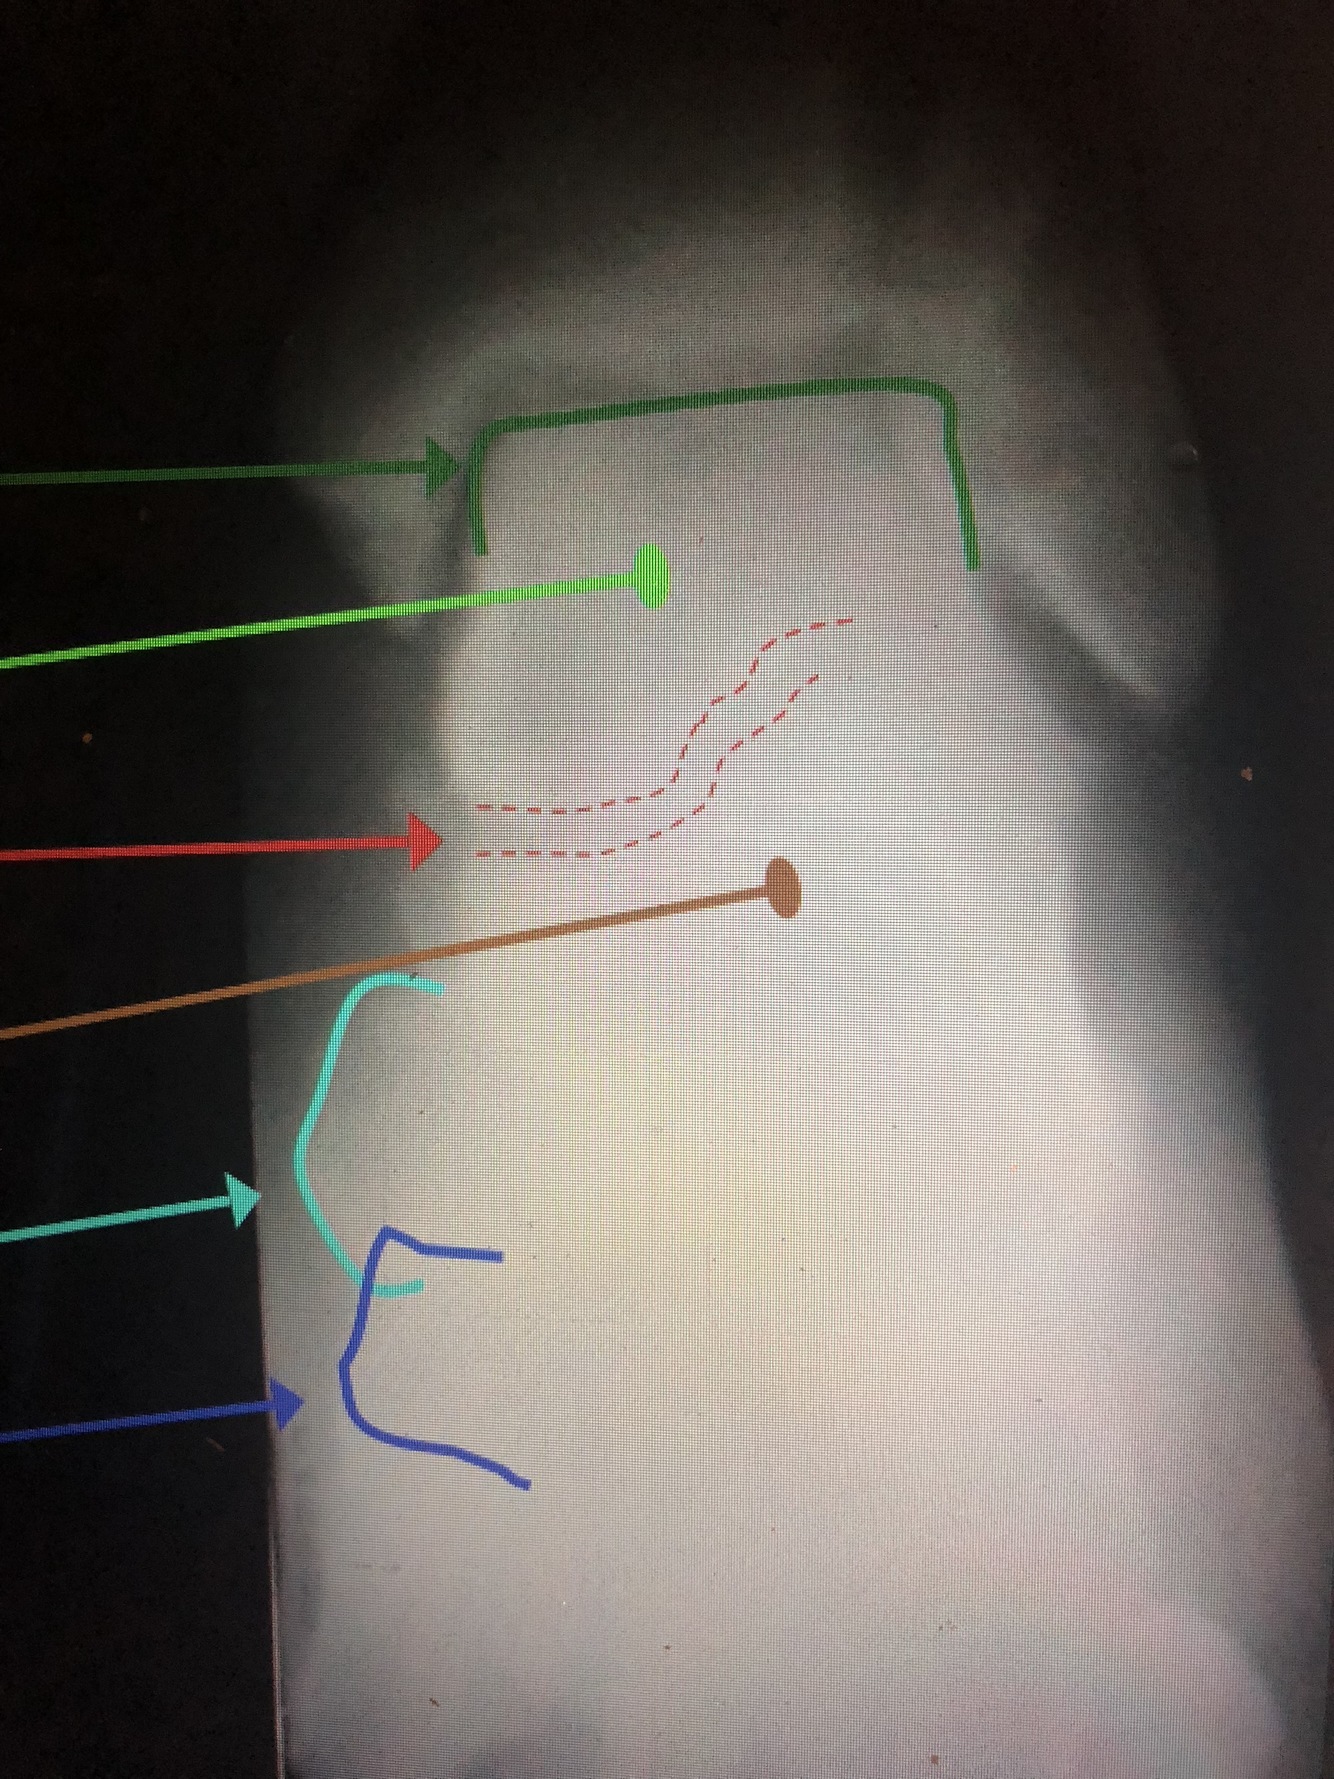

What is the dark blue line?

Interosseous Crest of the distal tibia

What is the light blue dotted line?

Fibular Notch

What is the red dotted line?

Posterior Malleolus

What is the green?

distal Fibular Shaft

What is the red?

Lateral Malleolus

Malleolar Fossa

What is the dark green line?

Talar Dome (Trochlea)

Which bone is the light green?

Talus

What is between the red dotted lines?

Talocalcaneal (Subtalar) Joint

What bone is the brown?

Calcaneus

What is the light blue line?

Navicular Tuberosity

Medial Cuneiform